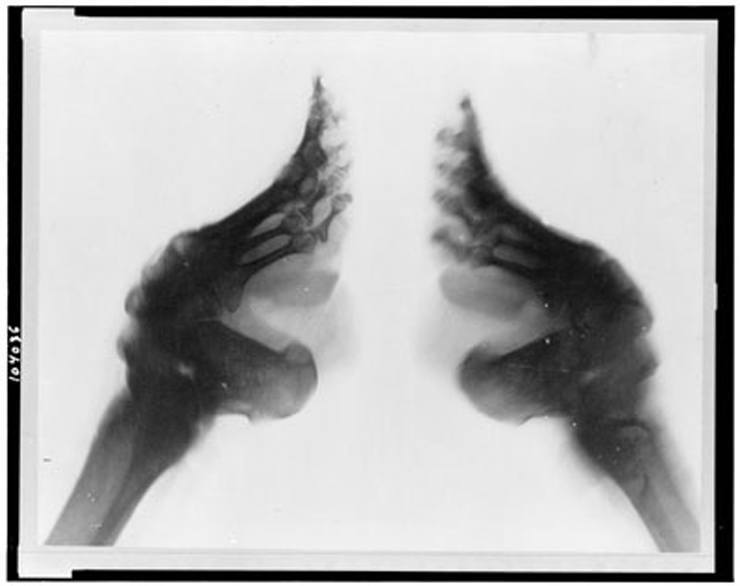

Рентген ног

На рентгеновском снимке китайская женщина с забинтованными ногами.